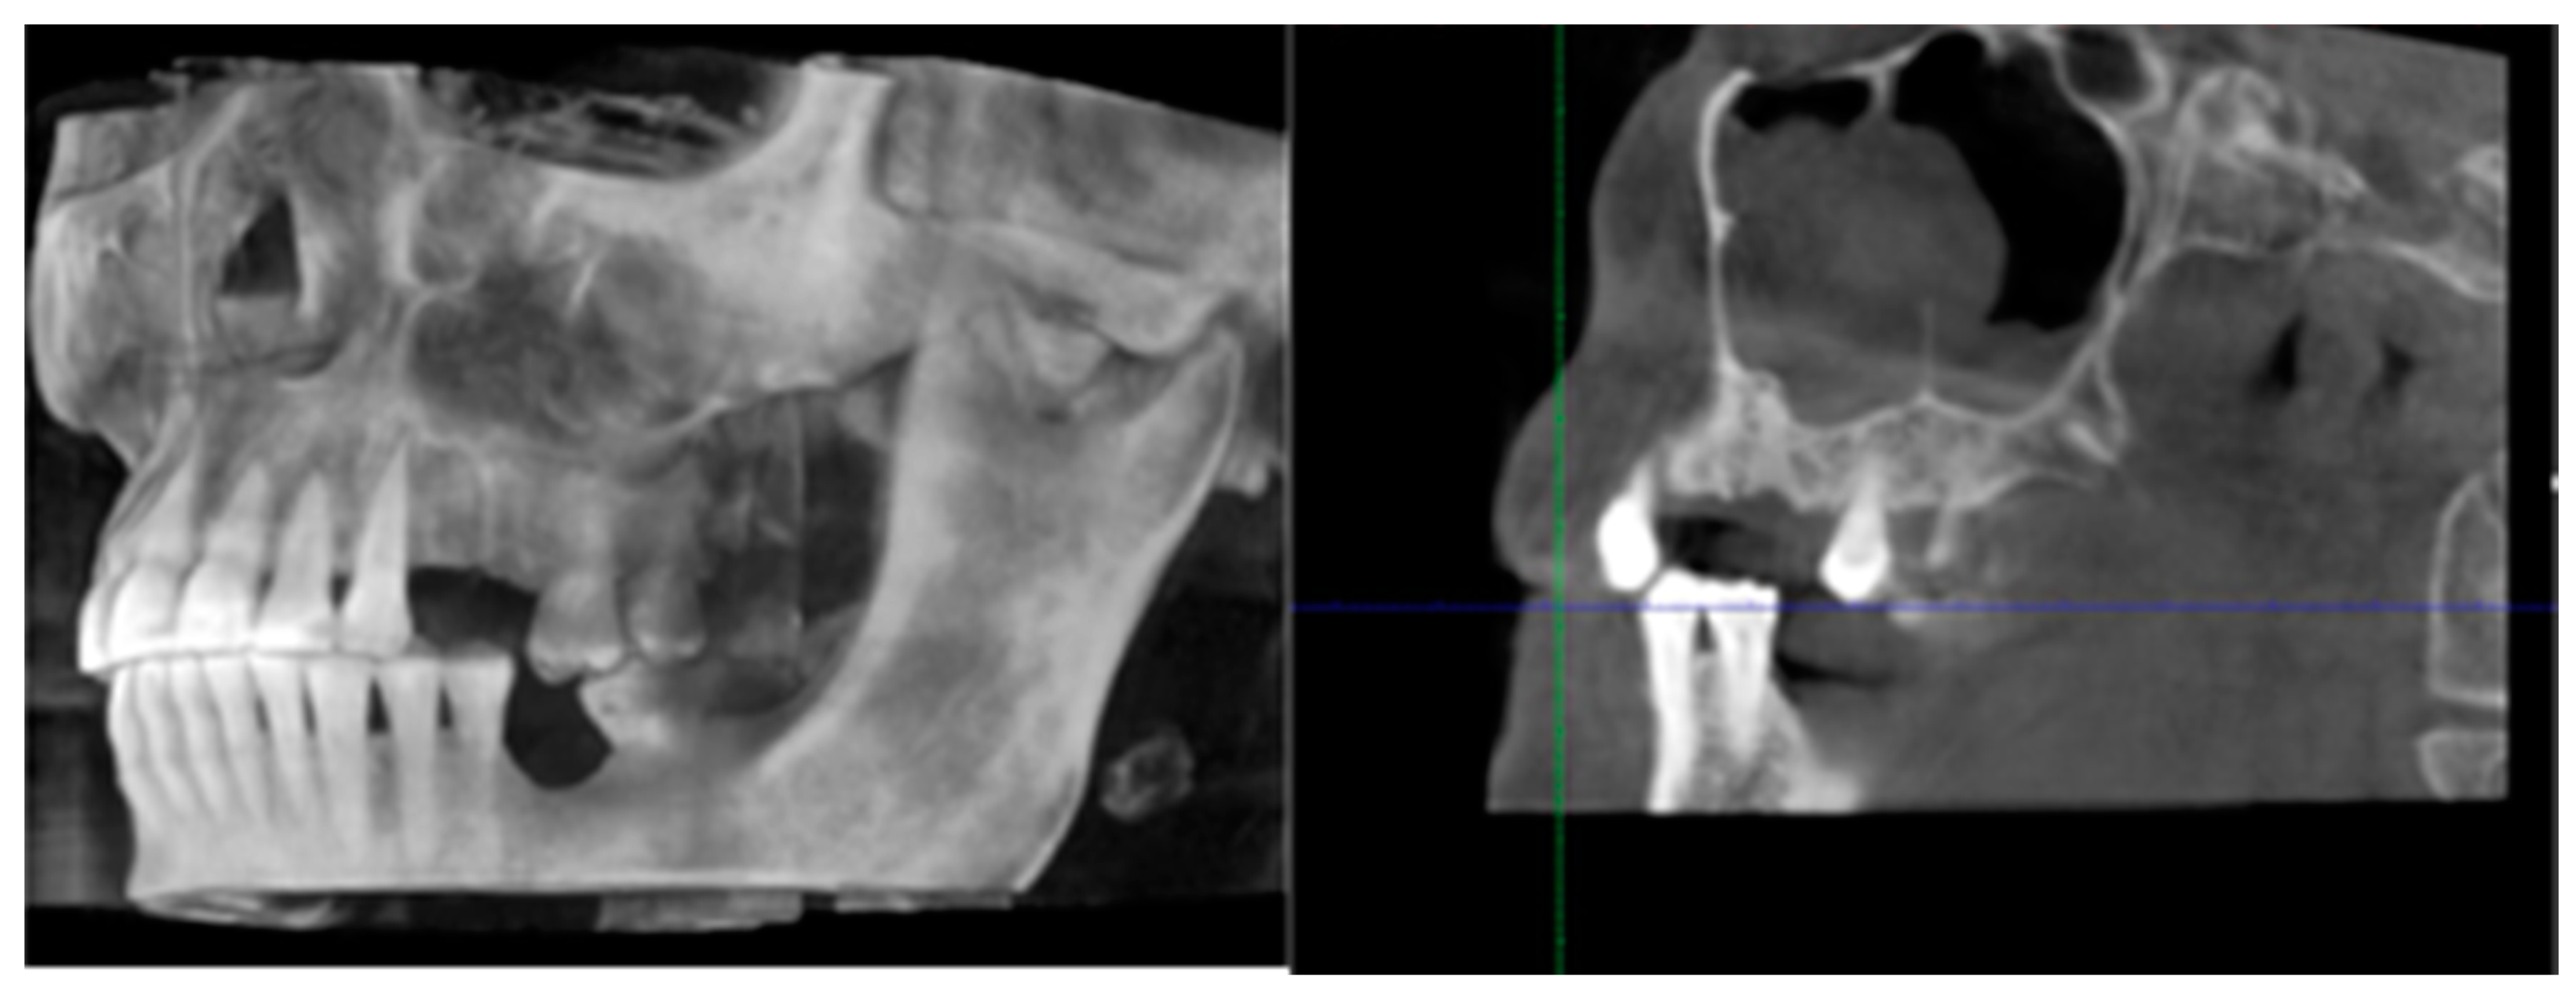

- Bedogni, A.; Fedele, S.; Bedogni, G.; Scoletta, M.; Favia, G.; Colella, G.; Agrillo, A.; Bettini, G.; Di Fede, O.; Oteri, G.; et al. Staging of osteonecrosis of the jaw requires computed tomography for accurate definition of the extent of bony disease. Br. J. Oral Maxillofac. Surg. 2014, 52, 603–608. [Google Scholar] [CrossRef]